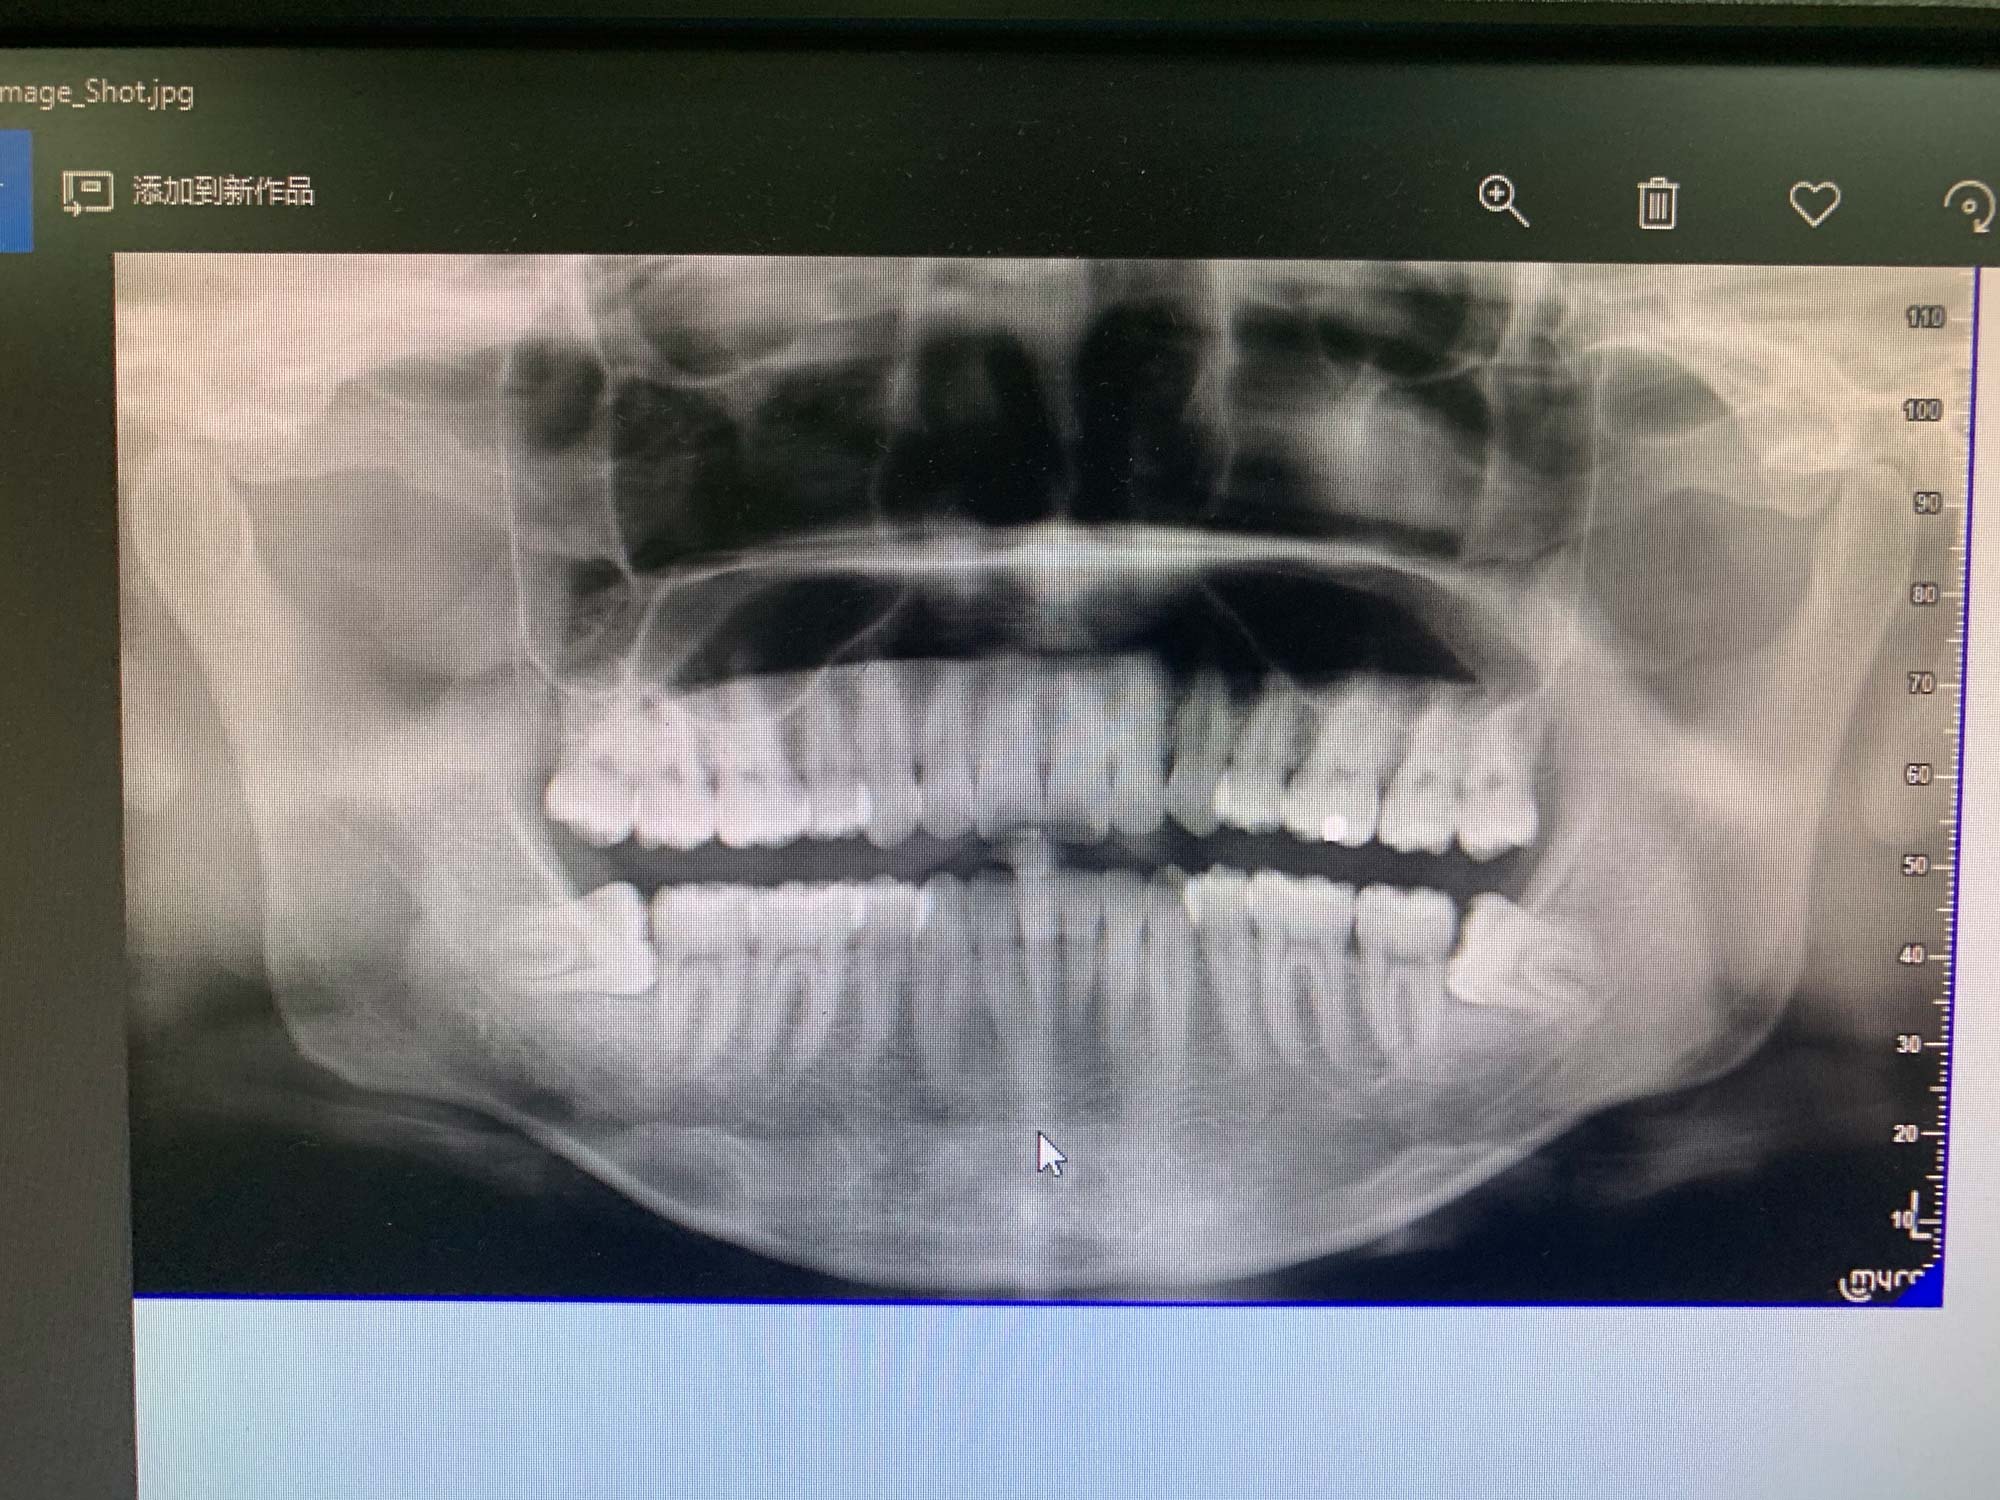

拍片检测费¥69元,可以刷医保,CT室就在一楼,等了一会,10分钟搞定,拍完后直接传到医生的电脑上,上面这就是我的片,可以看到,左右两边下方的阻生齿,位置还是挺尴尬的,如果不管的话,以后肯定会顶到并且损害旁边牙齿的牙根。